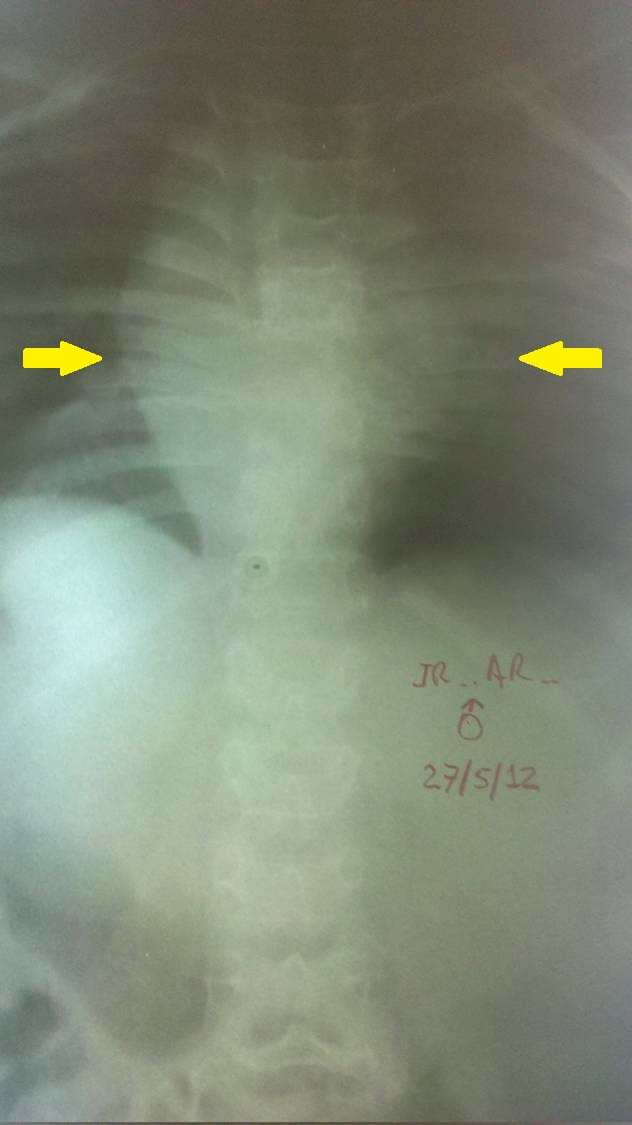

- Figura No 3a

- Figura No 3b

- Figura No 3c

- Figura No 3d

- Figura No 3e

- Figura No 3f

- Figura No 3g

- Figura No 3h

- Figura No 3i

- Figura 3 Texto